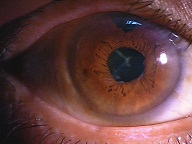

?正常な網膜です。中心部の赤い部分の網膜には、物を見るための視細胞が沢山集まっています。その周りの青にも、視細胞がありますが、赤に比べると数が少なくなります。緑はさらに見え方が落ちる部位です。